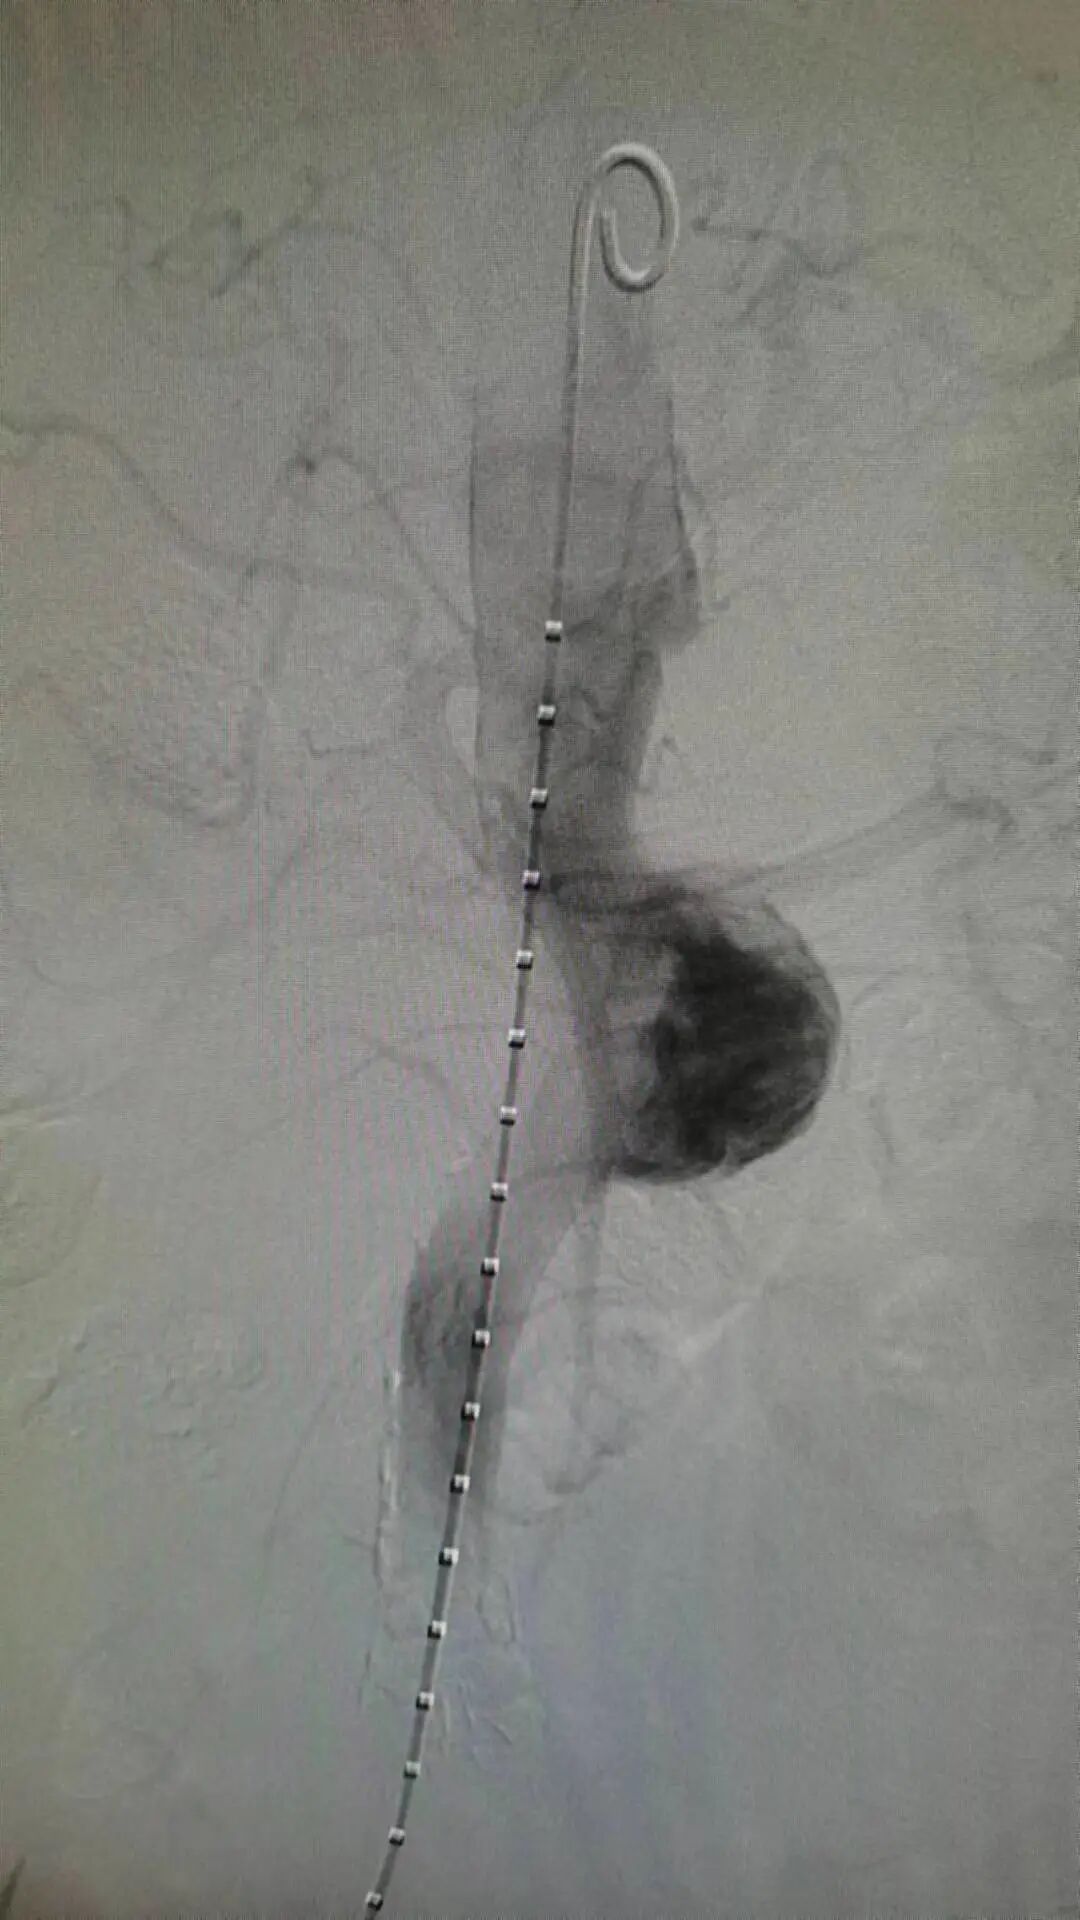

▲术前测量腹主动脉主要分支走向及角度

▲术前测量双侧肾动脉开口方位

“拆弹”小分队仔细地评估了患者术前的影像,包括瘤体的位置、大小、重要分支血管开口的位置及直径,详细制定介入手术的入路、支架放置的位置及先后顺序等计划。一切准备就绪,“拆弹”小分队迅速为患者进行介入治疗。